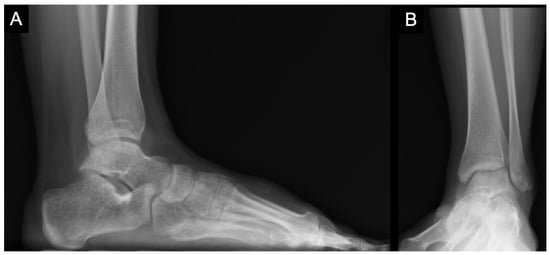

3. Diagnostics

4. Treatment